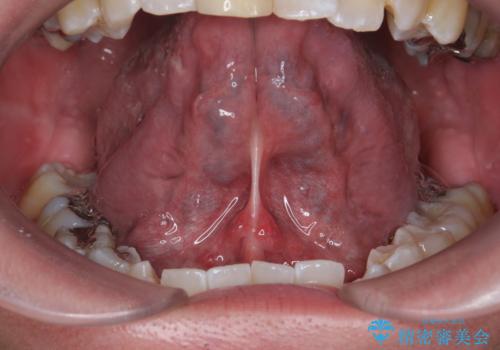

- 滑舌が気になるため舌小帯を切りたいとのことで来院された患者様です。

舌小帯切除を行い、滑舌の改善をはかります。

治癒も良好で、しゃべりやすくなったと大変喜んでいただけました。